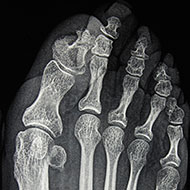

L’alluce valgo è una deformazione della parte anteriore del piede, conseguenza di una deviazione dell’alluce verso le altre dita del piede. Questo spostamento causa un tipico rigonfiamento laterale a livello della testa del primo metatarso. L’angolo tra il metatarso dell’alluce e quello del secondo dito si modifica progressivamente, con spostamento della base dell’alluce verso l’esterno. Questa deformità ossea è di solito associata a un’infiammazione costante o recidivante della borsa mucosa che si trova alla base dell’impianto dell’alluce stesso. Il sintomo principale dell’alluce valgo consiste nella presenza di dolore, che riflette un cambiamento nell’anatomia del piede. La deviazione laterale dell’alluce evidenzia la formazione della cosiddetta “cipolla“, una protuberanza che indica un’infiammazione molto dolorosa (borsite). Se l’alluce valgo viene trascurato, tende a peggiorare in maniera progressiva: il disturbo inizia con l’alluce rivolto verso il secondo dito, fino a determinare cambiamenti nell’allineamento effettivo delle ossa del piede. Nel corso degli anni, infatti, si possono instaurare anche deformità delle altre dita e forti dolori al piede (metatarsalgie).

Lo schema mostra che l’alluce è deviato lateralmente (valgo). Colpisce maggiormente la “cipolla” costituita dalla sporgenza sotto la pelle della testa del 1° metatarsale; urta contro la scarpa e causa infiammazione e dolore.

- 1. ALLUCE VALGO = spostamento laterale dell’alluce;

- 2. METATARSO VARO = spostamento verso l’interno del 1° metatarso.